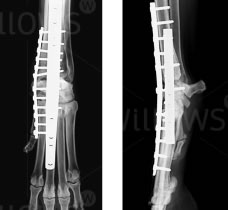

Pic 2: Arthrodesis of a carpus (wrist) in a Border Collie